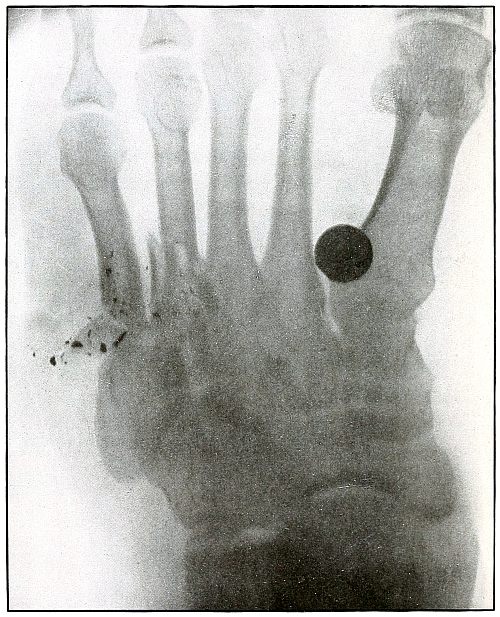

| 154. |

Gunshot wound, foot |

318 |

| 155. |

Gunshot wound, foot |

320 |

| 156. |

Gunshot wound, foot, multiple |

322 |